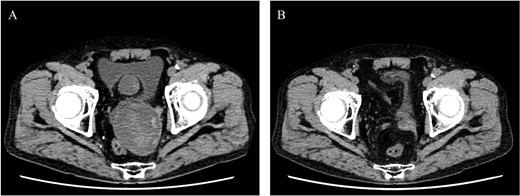

He underwent surgery under general anesthesia. A midline abdominal incision and an intraperitoneal approach were employed. Due to the aneurysm’s size, combined with adhesions to the surrounding intestines and the thinness of the aneurysm wall, achieving complete exposure was particularly challenging. Therefore, the aneurysm was incised midway. The hematoma and coils were removed, and the feeding vessels were ligated with 3–0 monofilament. Blood oozing from the feeding vessels suggested that the aneurysm expansion was likely due to a type II endoleak that was not visible on contrast-enhanced CT. The laparoscope was used to observe the aneurysm, identify, and ligate the inflow vessels that were difficult to visualize directly (Fig. 2). The IIA was sutured with 3–0 monofilament using laparoscopic assistance, taking care to avoid including adjacent structures such as the rectum in the sutures. The operation took 255 min, and the patient was discharged on the fourteenth day postoperation. Follow-up CT at 10 months postoperation showed a reduction in aneurysm size (Fig. 3).

Laparoscopic view of the orifice of the feeding vessel (blue arrow).

Postoperative computed tomography showing a reduction in aneurysm size. A—Preoperative image, B—10-month postoperative image.